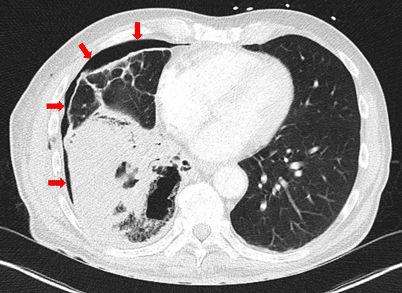

Im Labor zeigten sich eine Leukozytose (27,44 ∙ 109/l) sowie ein erhöhtes CRP (325 mg/l). In der Röntgenuntersuchung des Thorax wurde ein rechtsseitiger Spannungshydropneumothorax mit Verlagerung des Mediastinums nach links und einem Flüssigkeitsniveau auf Höhe der rechten, dritten Rippe festgestellt (Abb. 1).

Abb. 1

Röntgenuntersuchung des Thorax mit Spannungshydropneumothorax der rechten Lunge mit Verlagerung des Mediastinums nach links, zudem Flüssigkeitsniveau des Spannungspneumothorax auf Höhe der rechten dritten Rippe (weiße Pfeile)